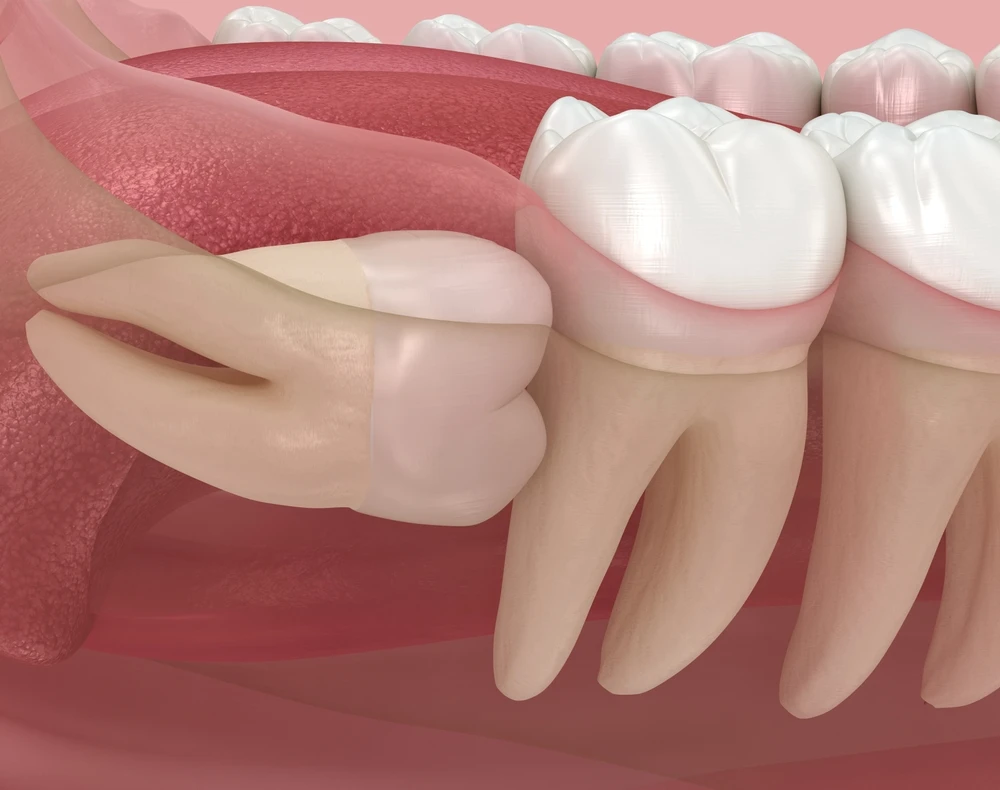

Dodatkowym wskazaniem jest diagnostyka ósemek w sąsiedztwie korzeni drugich trzonowców dolnych. Resorpcja dystalnego korzenia siódemki przez zatrzymaną ósemkę to powikłanie typowo skryte, odkrywane czasem dopiero gdy siódemka jest nie do uratowania. CBCT wykonane z wyprzedzeniem pokazuje, jak bliskie jest sąsiedztwo i czy bieżące ułożenie ósemki stwarza ryzyko – zanim dojdzie do nieodwracalnego uszkodzenia korzenia.

Na tej samej zasadzie CBCT stosowane jest przy diagnostyce zatrzymanych kłów dziecięcych, zębów nadliczbowych (mezjodensu) wciśniętych między korzenie siekaczy i anomalii liczby zębów. Każdy przypadek, gdzie trójwymiarowa lokalizacja zęba wpływa na plan zabiegu chirurgicznego lub ortodontycznego, jest potencjalnym wskazaniem do badania.

- Orientacja przestrzenna zatrzymanego zęba – strona dostępu chirurgicznego (wargowa/podniebienna/językowa) widoczna bezpośrednio; eliminuje najczęstsze zaskoczenie śródoperacyjne

- Relacja do korzeni sąsiednich – odległość i kontakt z korzeniami sąsiednich zębów mierzalne w milimetrach; ryzyko uszkodzenia identyfikowane przed nacięciem

- Resorpcja korzenia siódemki przez ósemkę – typ i zasięg uszkodzenia widoczny na CBCT zanim jest klinicznie lub radiologicznie wykrywalny na projekcji 2D; decyzja o ekstrakcji ósemki z wyprzedzeniem

- Grubość kości nad koroną zatrzymanego zęba – grubość blaszki kostnej zmierzona przed zabiegiem; lekarz planuje technikę i zasięg preparacji przed pierwszym cięciem